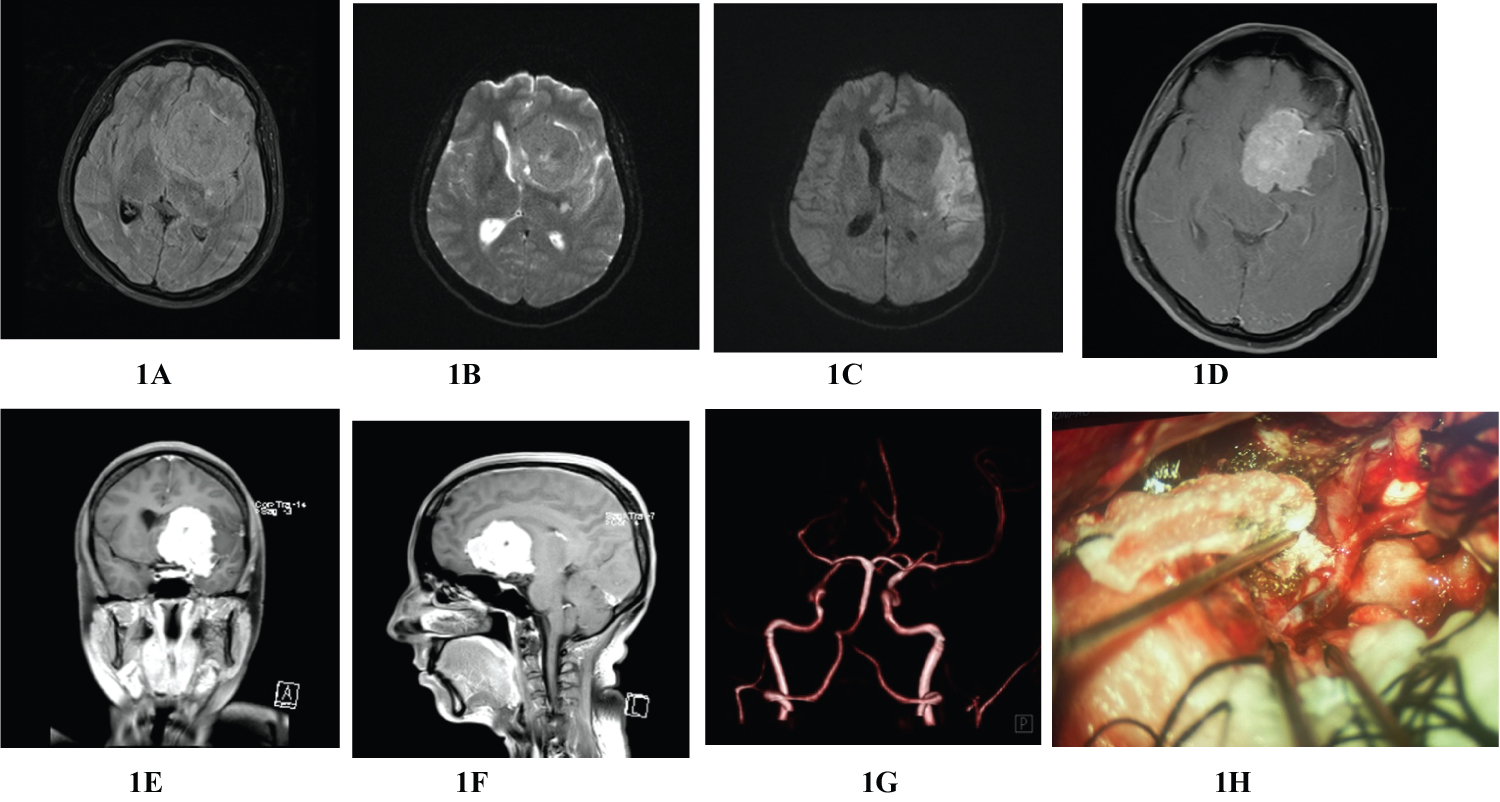

A 36-year-old right-handed female without significant medical comorbidity was brought to Emergency and Accident (A&E) Department with the history of sudden onset of severe headache followed by vomiting and unconsciousness for 24 hours. She was referred to our center after initial resuscitation at another hospital. On arrival, her GCS was 11 with eye opening three, motor score 5 and verbal score three. He was hemiplegic on right side. There was anisocoria with left pupil dilated, fixed and not reacting to the light; her right pupil was normal and reacting to the light. Contrast MRI of the Brain showed left sided homogenous enhancing extra axial mass attached to medial sphenoid wing and planum sphenoidal area encasing the left internal carotid artery (ICA) and M1 segment of left MCA (Figure 1A, Figure 1B, Figure 1D, Figure 1E and Figure 1F). MRA showed complete occlusion of left MCA at M1 segment (Figure 1G). T2/FLAIR image revealed hyperintense area in left MCA territory suggestive of infarct (Figure 1C).

Figure 1: Preoperative MRI of brain; T1W & T2W images showing large solid mass at left frontotemporal region with midline shift (1A and 1B), T1/FLAIR image depicting left frontotemporal mass with MCA territorial infarct (1C), contrast MRI of brain with axial, coronal and sagittal sections showing large extraaxial homogenously enhancing left frontotemporal mass attached to medial sphenoid, clinoid and planum sphenoidal areas (G-F), MRA revealing total occlusion of left MCA at A1 segment (G), intraoperative picture showing intraluminal thrombus (black segment) at left M1 segment causing total occlusion of artery (H). View Figure 1